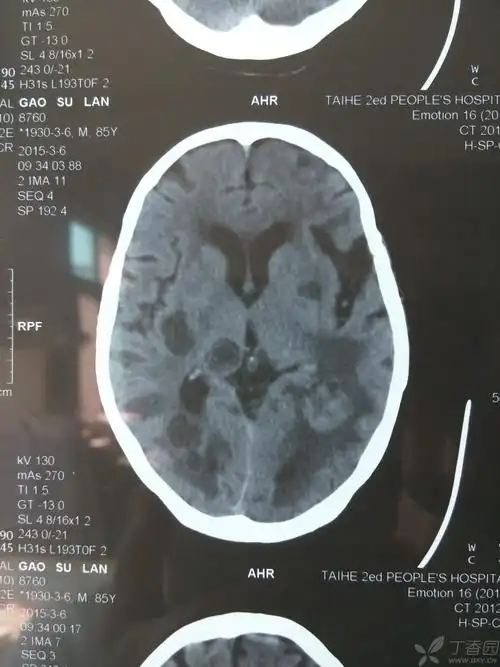

从形状看不像脑梗死,病人家属不愿再花钱查磁共振.